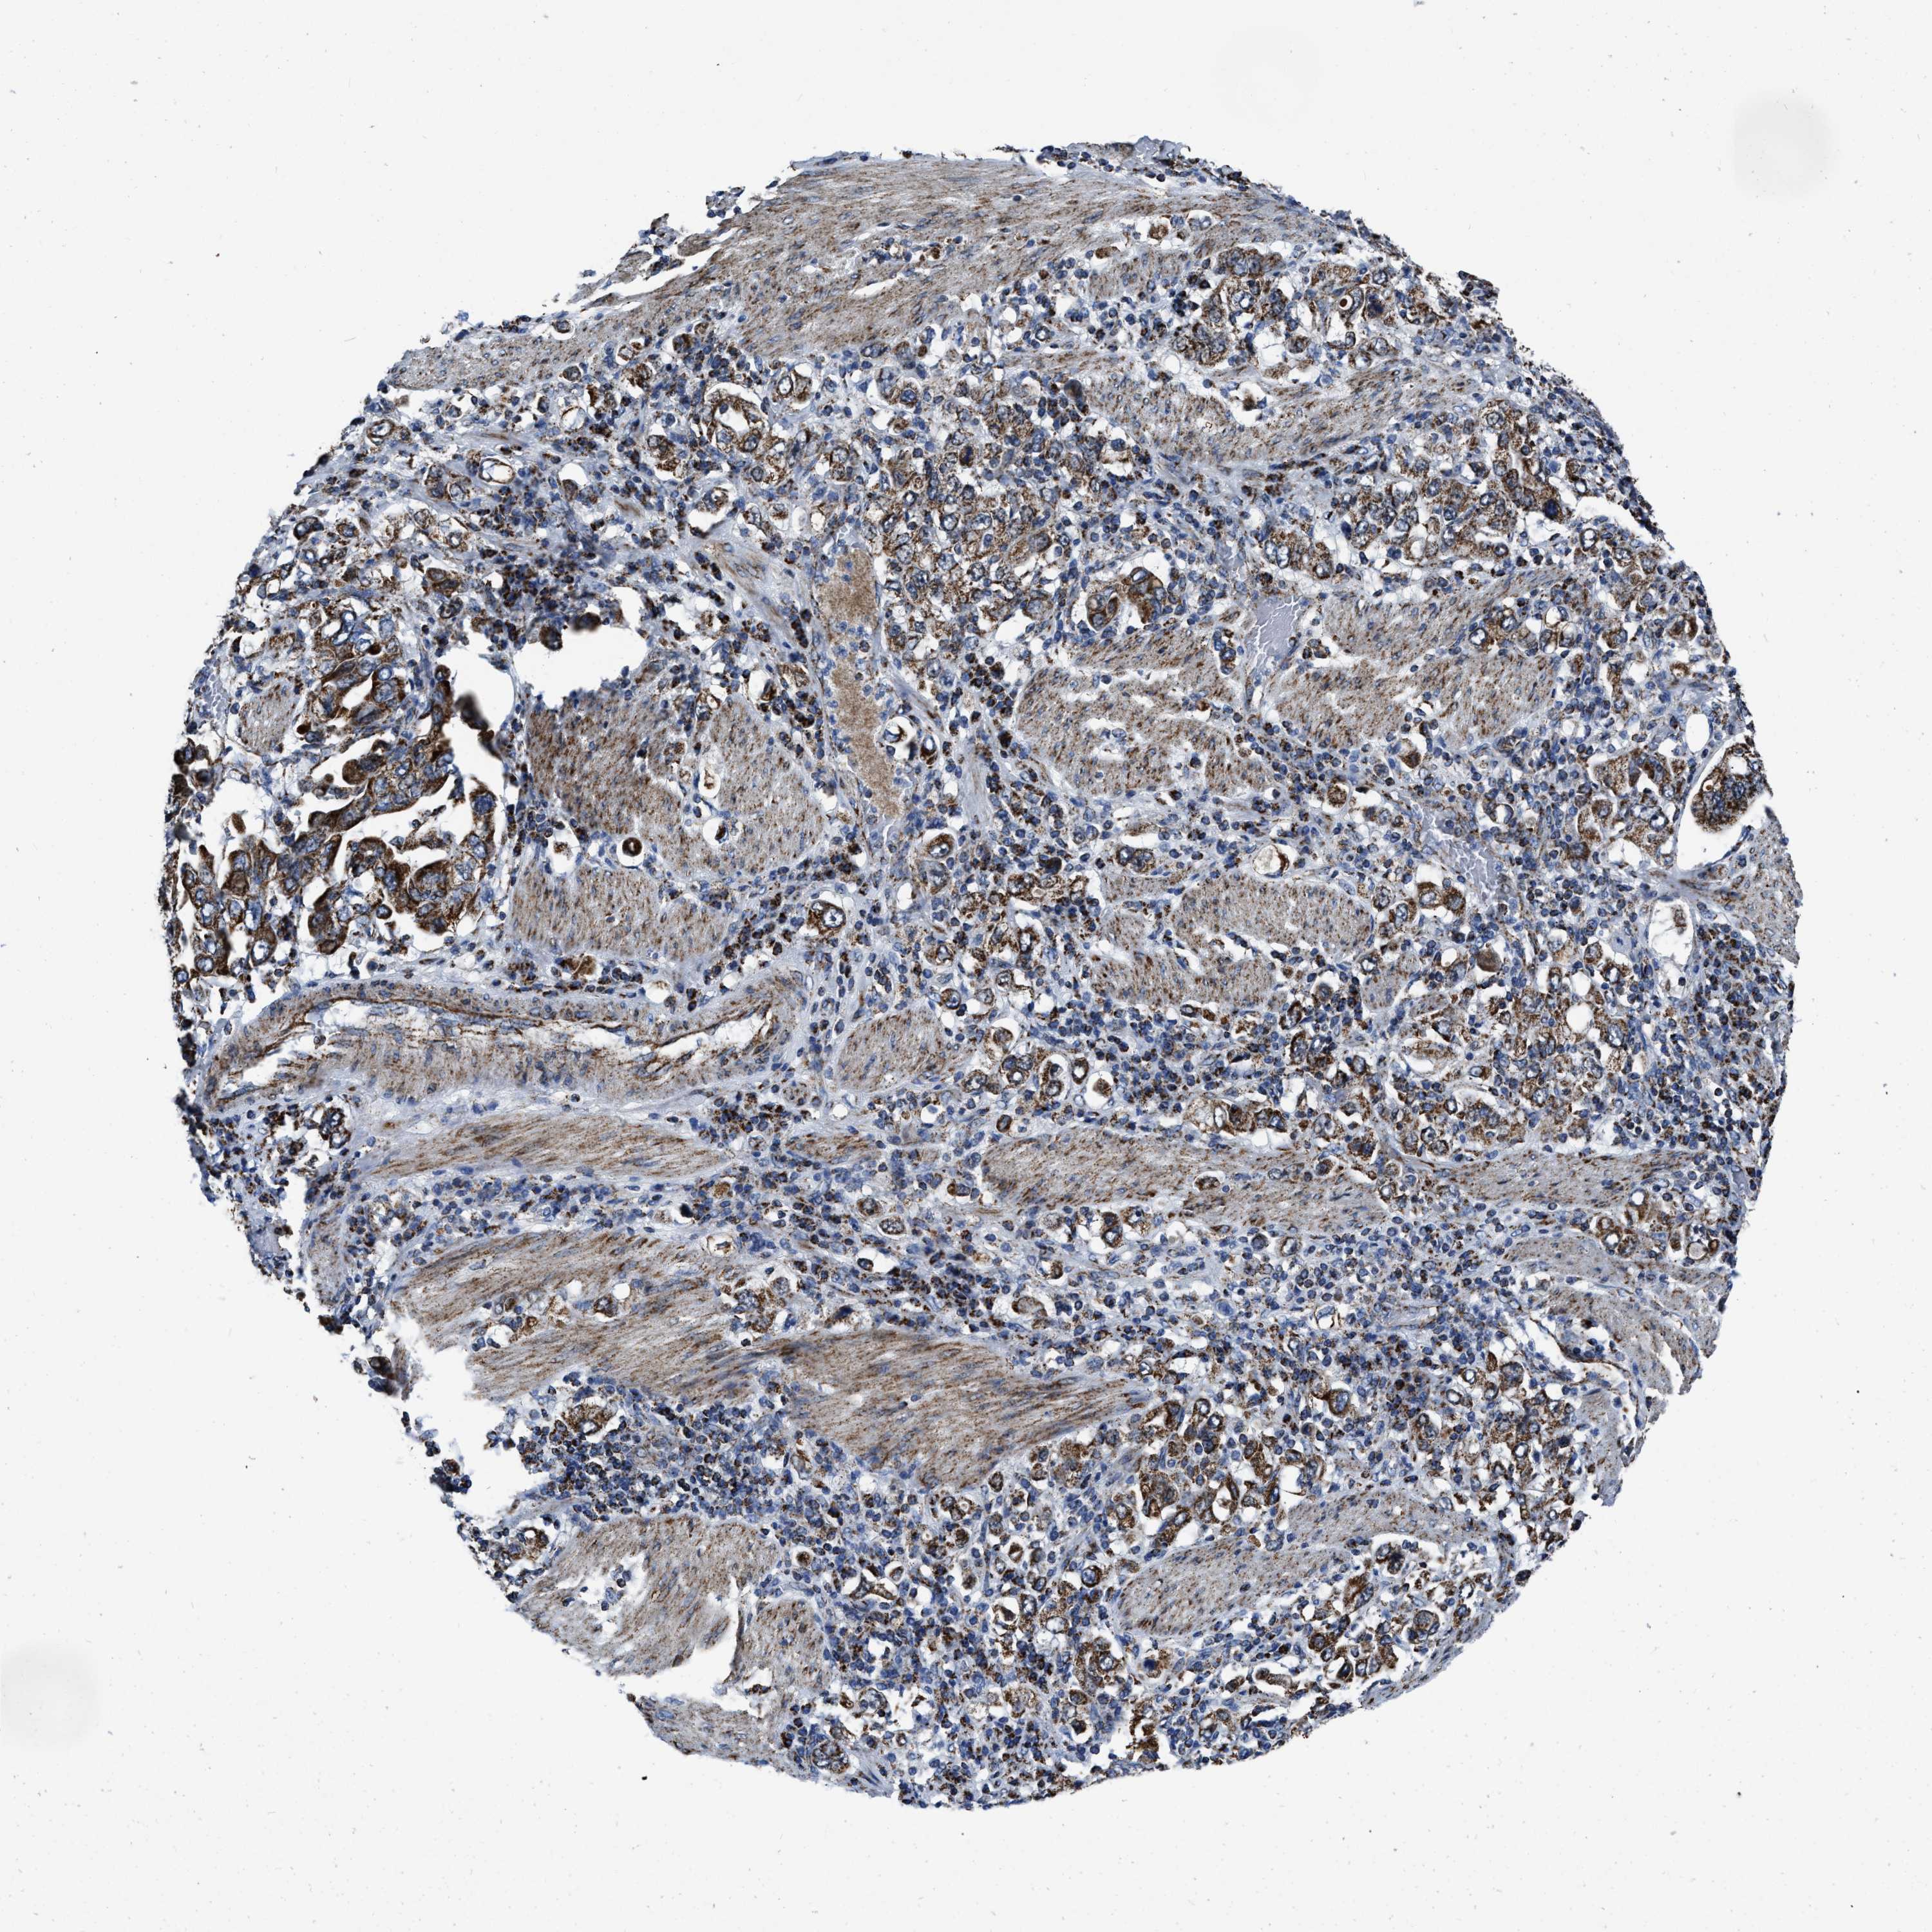

STOMACH CANCER - Protein expressioni

A mouse-over function shows sample information and annotation data. Click on an image to view it in a full screen mode. Samples can be filtered based on level of antibody staining by selecting one or several of the following categories: high, medium, low and not detected. The assay and annotation is described here.

Note that samples used for immunohistochemistry by the Human Protein Atlas do not correspond to samples in the TCGA dataset.

Antibody stainingi

Antibody staining in the annotated cell types in the current human tissue is reported as not detected, low, medium, or high, based on conventional immunohistochemistry profiling in selected tissues. This score is based on the combination of the staining intensity and fraction of stained cells.

Each image is clickable and will lead to virtual microscopy that enables deeper exploration of all samples and also displays staining intensity scores, fraction scores and subcellular localization as well as patient and tissue information for each sample.

Antibody HPA018893

Staining

High

Medium

Low

Not detected

Intensity

Strong

Moderate

Weak

Negative

Quantity

>75%

75%-25%

<25%

None

Location

Nuclear

Cytoplasmic/membranous

Cytoplasmic/membranous,nuclear

Adenocarcinoma, NOS